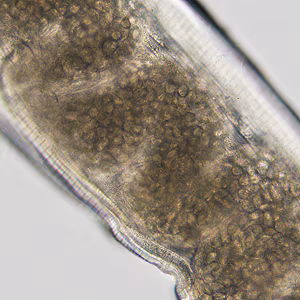

A 26-year-old man was seen by his health care provider for the sensation of something moving in his mouth. He reported a history of such sensations since he was age 12. He was referred to an otolaryngologist who observed a serpentine-like lesion, with possible movement, in the lateral left soft palate. A worm-like structure was removed surgically and sent to the DPDx Team for identification. Figure A shows a gross image of the entire worm. Figures B and C show the anterior and posterior ends, respectively, and were captured at 100x magnification. Figure D shows the mid-section, captured at 200x magnification. What is your diagnosis? Based on what criteria?

Figure D